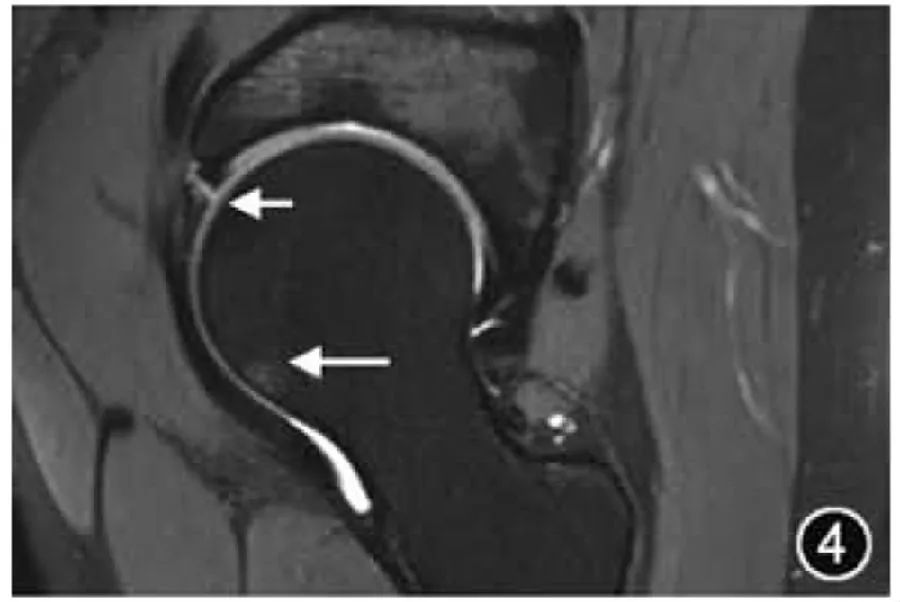

3.ФАИ: ФАИ вызывается контактом и столкновением проксимального отдела бедренной кости с краем вертлужной впадины, что может привести к поражению вертлужной впадины, верхней губы и хряща, вызвать боль и дисфункцию, а также может привести к раннему началу ОА. Патогенез ФАИ может быть обусловлен чрезмерным охватом глубокой вертлужной впадины (тип клещей, также известный как тип клещей) и/или недостаточной депрессией в месте соединения головки и шейки бедренной кости (тип кулачка, также известный как тип кулачка). Две анатомические аномалии часто возникают одновременно (гибридные). Визуализирующее лечение и оценка FAI должны сначала провести обзорное рентгенологическое исследование таза в передне-задней части. Пациенты с симптомами должны пройти обследование положения стрелки и компьютерную томографию для комплексной оценки морфологии вертлужной впадины, головки и шеи бедренной кости. МРТ также является важным средством комплексной оценки FAI, в основном фокусируясь на оценке степени и степени повреждения верхней губы и хряща. Передняя часть губы является основным местом повреждения FAI (рис. 4). Следует отметить, что диагноз ФАИ можно поставить только при одновременном появлении типичных визуализирующих признаков и клинических симптомов.

Рисунок 4. МРТ-изображение ушиба бедра. Корональный Т2-ВИ: разрыв латеральной верхней губы вертлужной впадины (короткий ↑), сопровождающийся отеком костного мозга в месте соединения головки и шейки бедренной кости (длинный ↑).